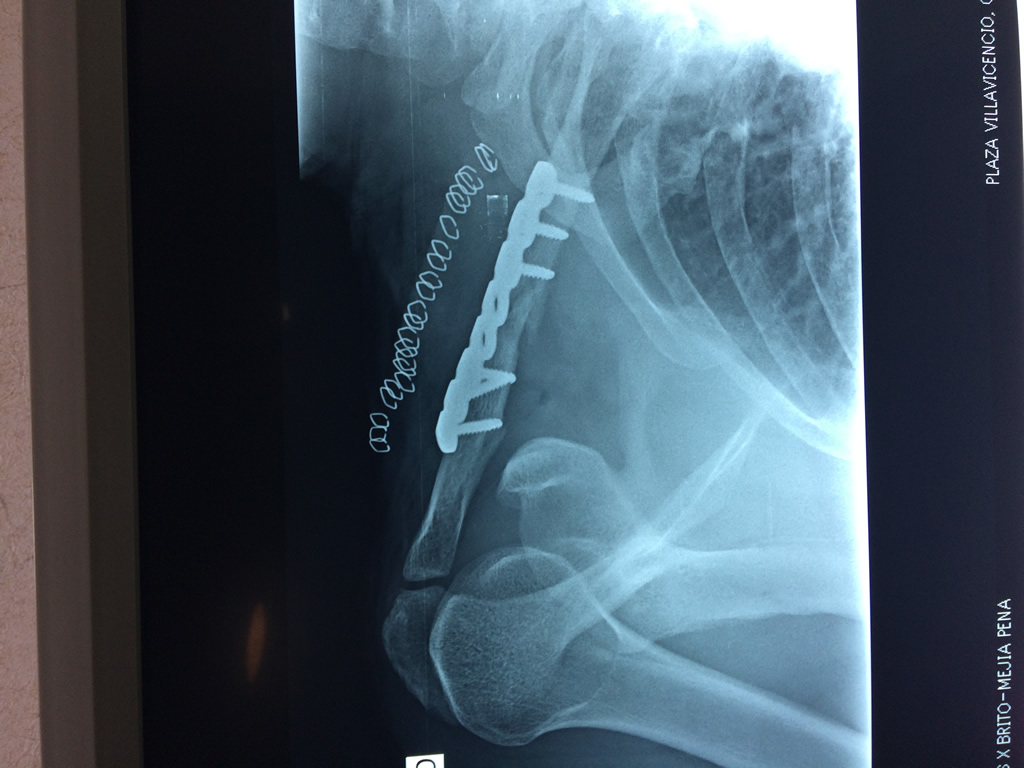

Cirugias en El Salvador - Clavícula

La clavícula es un hueso largo, con forma de "S" itálica, situado en la parte anterosuperior del tórax. Junto con la escápula forman la cintura escapular. Se puede palpar por toda su longitud y se extiende del esternón al acromion de la escápula, siguiendo una dirección oblicua lateral y posterior.

Se considera el único medio de unión entre el miembro superior y el tórax. A pesar de su aspecto, similar al de un hueso largo, posee una estructura semejante a la de un hueso plano, ya que carece de epífisis y de diáfisis, lo que la harían entrar dentro de la clasificación de hueso largo. Carece de un canal medular propiamente dicho.